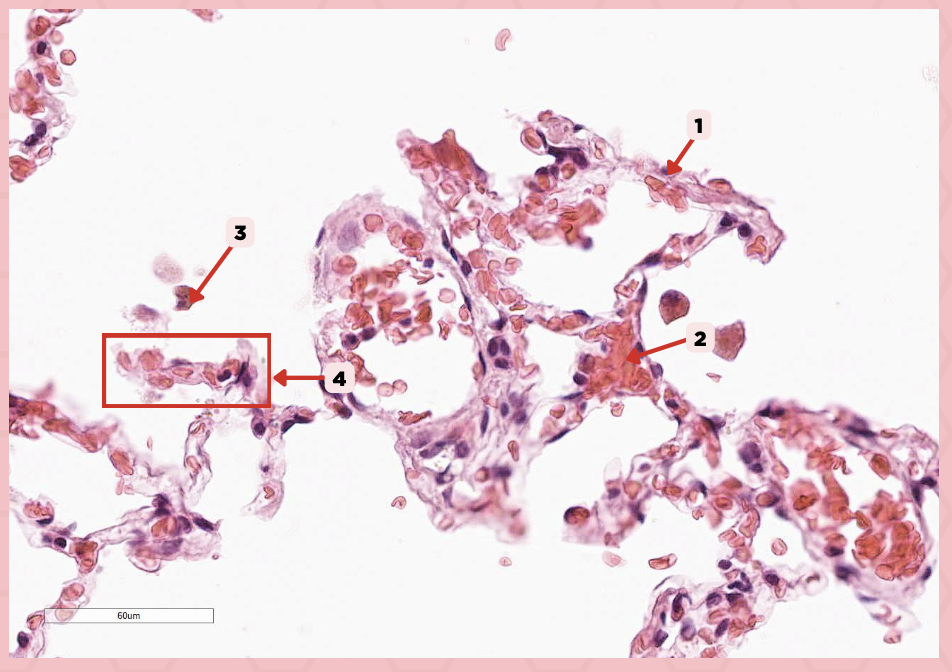

Interalveolar septum

Identify the structure labeled as 1.

Type I alveolar cell

Identify the structure labeled as 2.

Type II alveolar cell

Identify the structure labeled as 3.

Pulmonary Alveolar Macrophages (Dust Cells)

Identify the structure labeled as 4.

Pulmonary Alveolar Macrophages (Dust Cells)

What are the most numerous cells inside the alveoli?

Pneumocyte Type I

Which of the following labeled structures covers 95% of the alveolar surface?

Type I alveolar cell

Identify the structure labeled as 1.

Type II alveolar cell

Identify the structure labeled as 2.

Pulmonary Alveolar Macrophages (Dust Cells)

Identify the structure labeled as 3.

Endothelial Cells

Identify the structure labeled as 4.